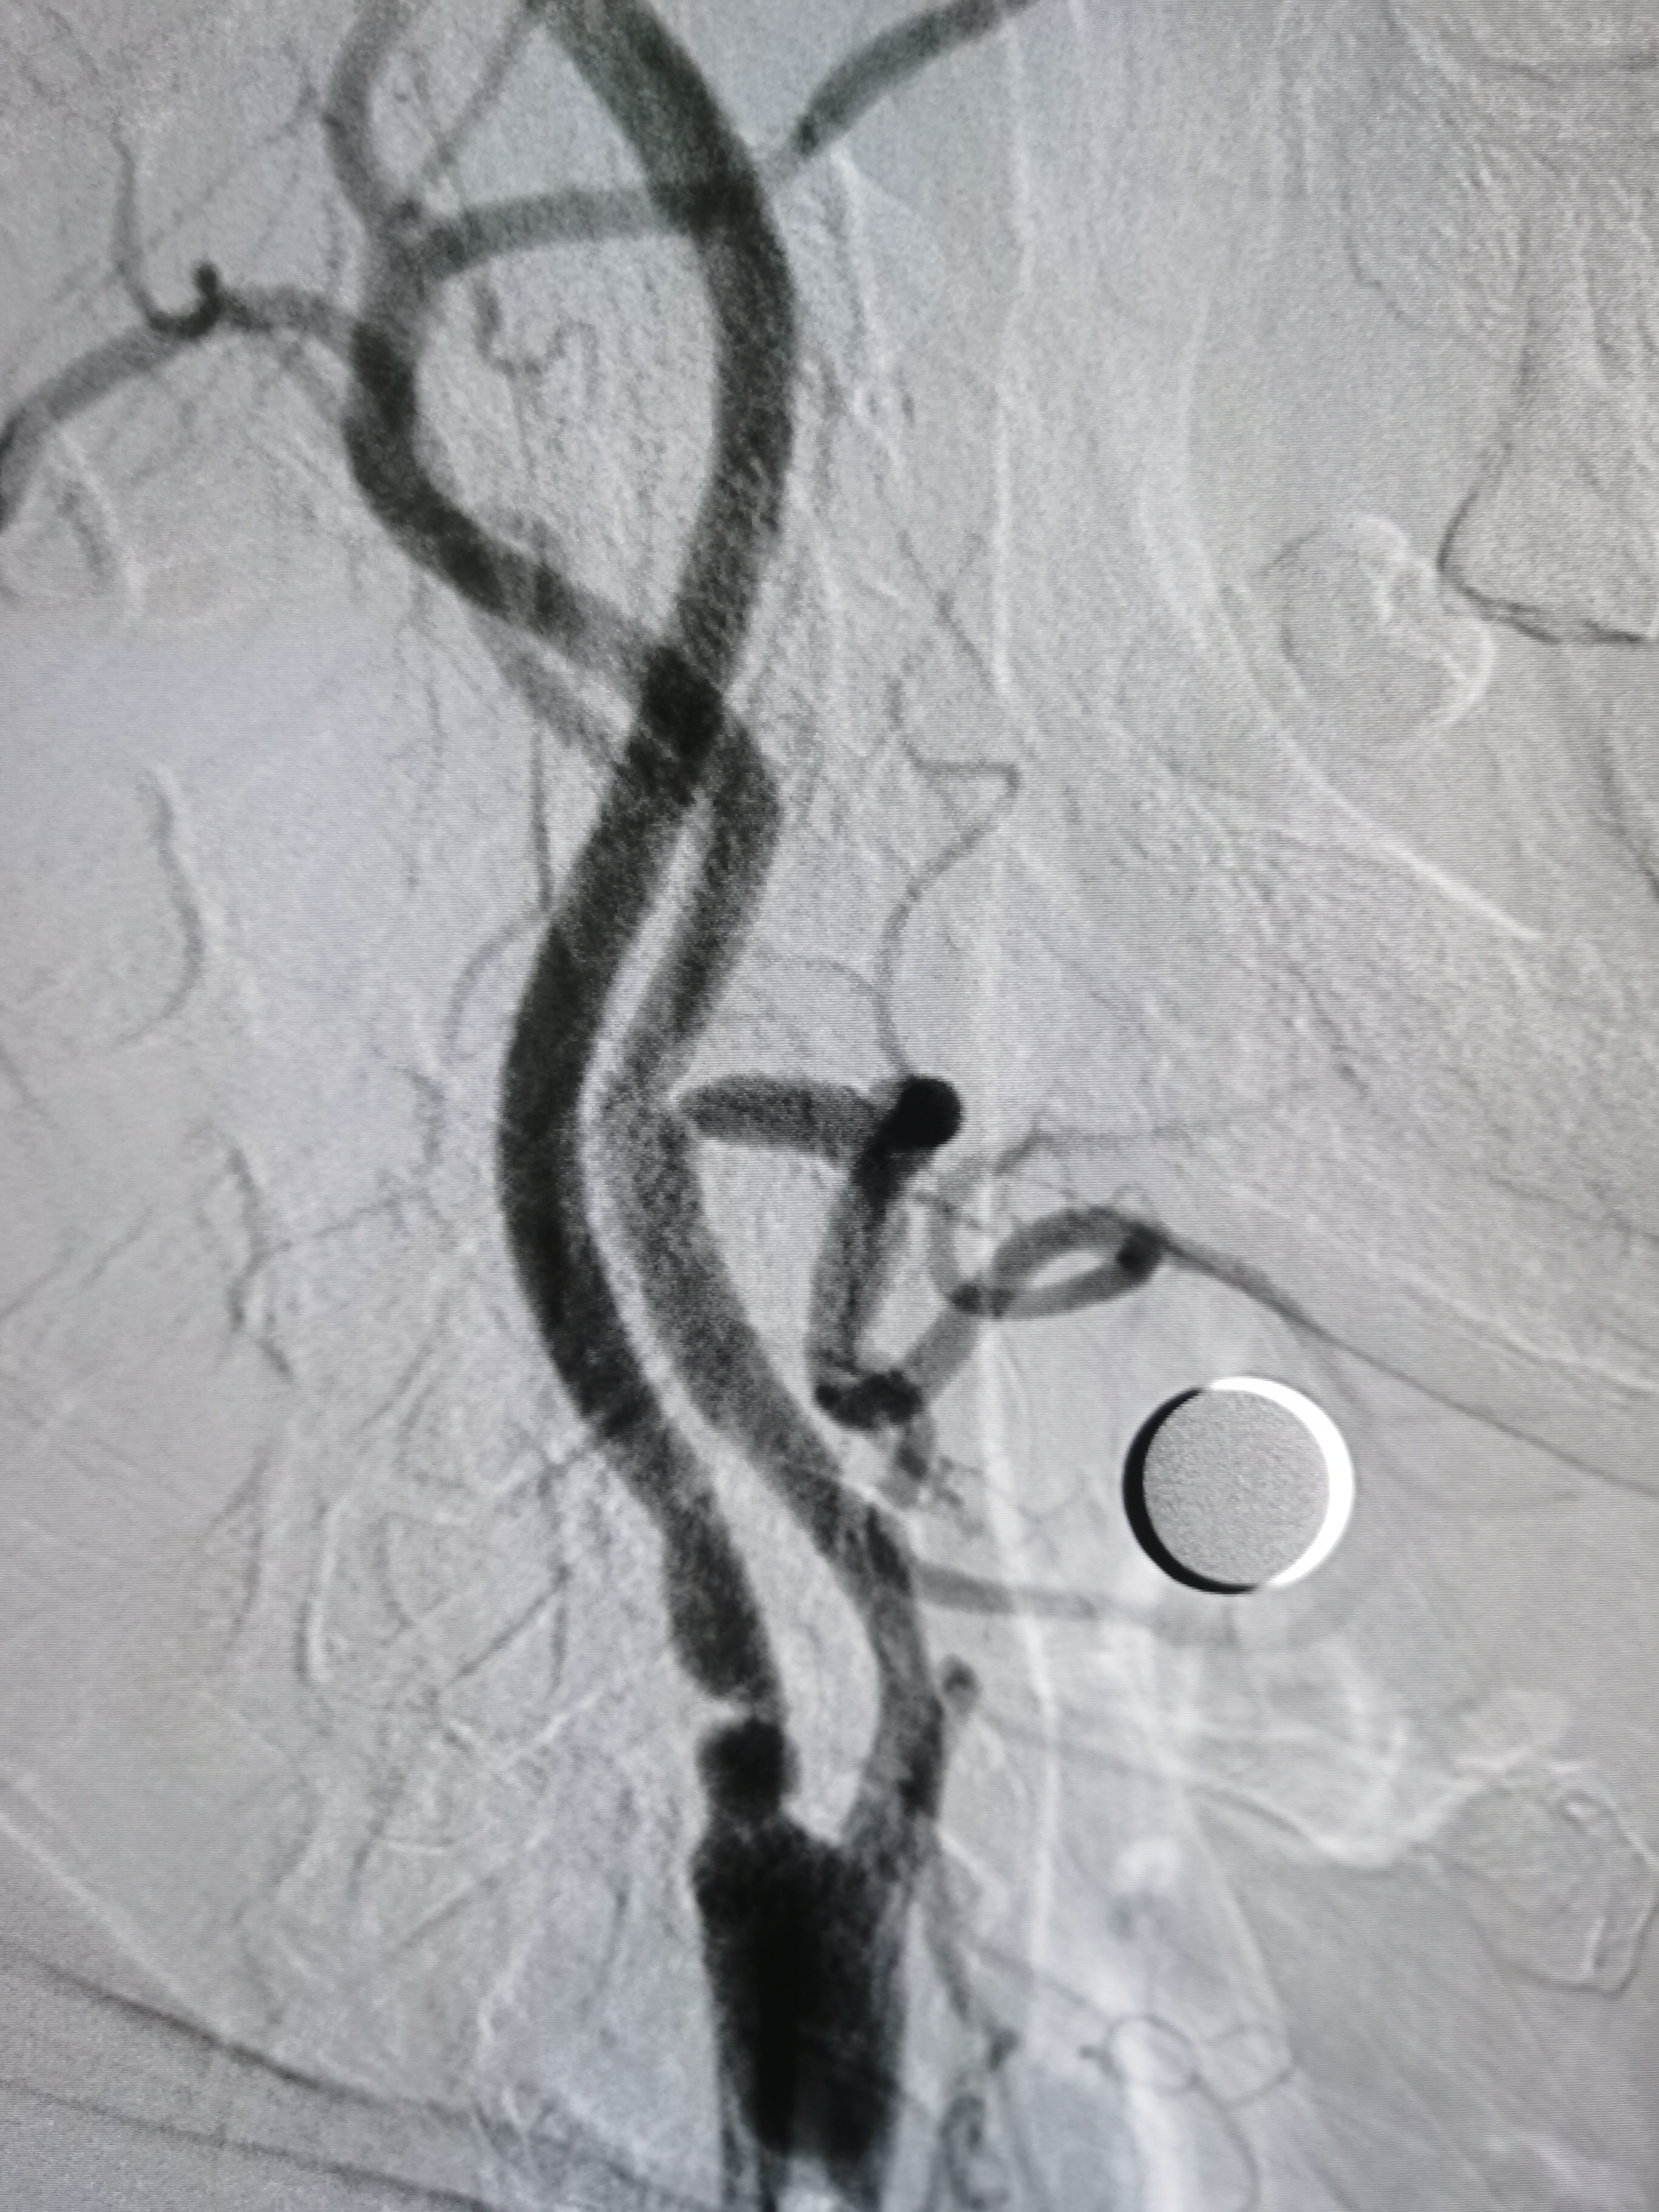

将导引导管调至左侧颈总动脉末端,远端置入保护伞。

9/30支架定位。

支架释放后狭窄改善,覆盖不稳定斑块。

支架释放后颅内血供良好。

颅内血供良好。